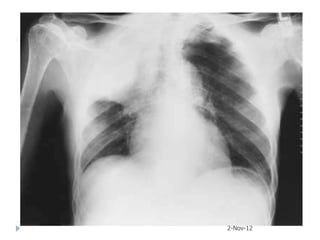

   65-year-old female presented with acute respiratory

failure. She had been sick for two weeks with fever,

confusion, diarrhea, cough, and purulent sputum

production. Her medical checkup two months ago

was unremarkable.

   Urea 11 mmol/L, Creatinine 3.2

   CXR and later CT chest obtained

2-Nov-12

After3 weeks course of macrolide